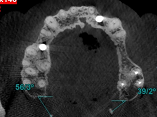

This special issue delves into the intricate world of head and neck disorders, encompassing the oral cavity, salivary glands, thyroid, pharynx, larynx, and craniofacial structures. Bridging the gap between foundational science and clinical innovation, this collection explores the full spectrum of diseases—from benign conditions like dental caries, periodontal disease, and temporomandibular joint disorders to malignancies such as oral squamous cell carcinoma, HPV-driven oropharyngeal cancers, and salivary gland tumors. By integrating dental, oral, and craniofacial health into the broader head and neck framework, this issue highlights the interconnectedness of these systems and their collective impact on patient well-being.